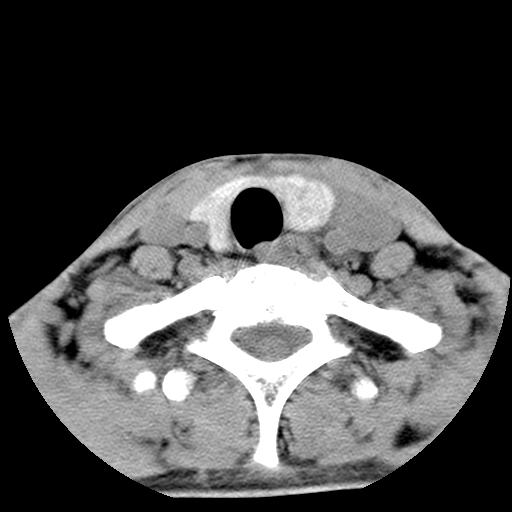

标题: CT15118:f-27y,左颈部肿一个月,无发热、无压痛 [打印本页]

标题: CT15118:f-27y,左颈部肿一个月,无发热、无压痛

1、甲状腺左叶病变:腺瘤?结节性增生?其他?

2、上极周围间隙病变。

3、2者关系?

左侧甲状腺肿大,密度不均.同侧甲状软骨似有破坏(建议传骨窗).左侧颈静脉增粗,各组织之间分界不清,有多个肿大淋巴结.甲状腺肿并感染?临床症状不符.淋巴结核?请结合其他检查.